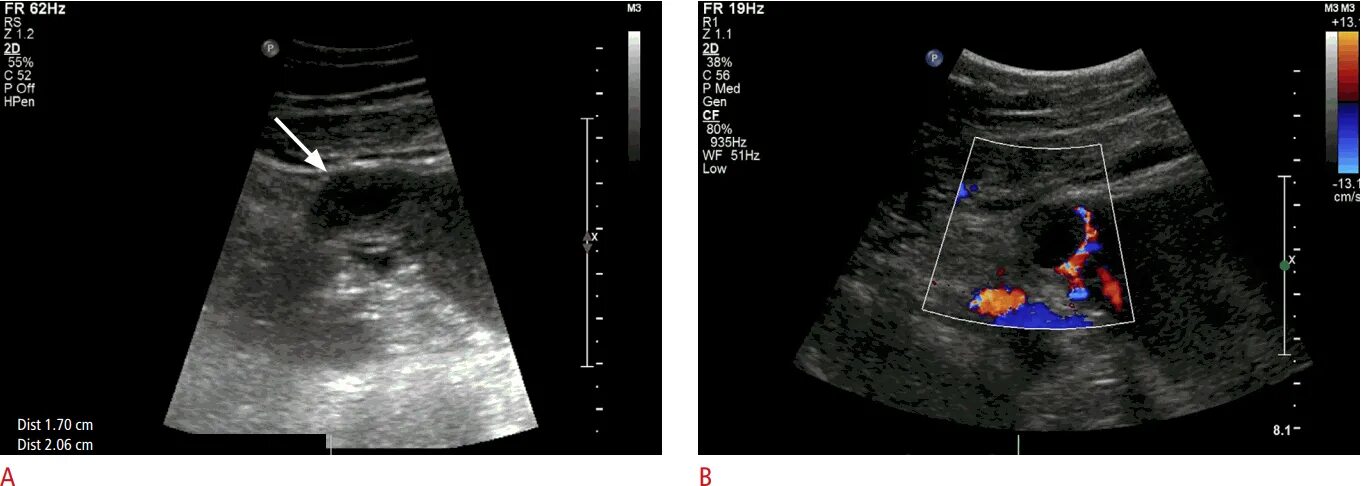

Можно ли на узи увидеть внематочную беременность